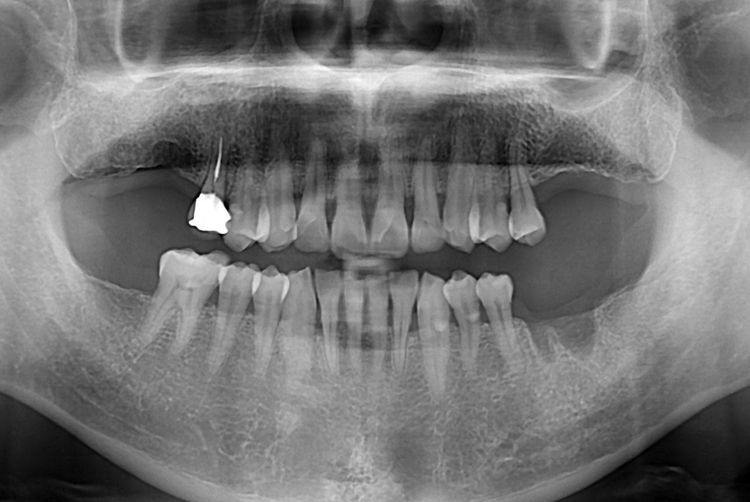

[임플란트] 어금니 임플란트

치료전 : 2017-08-28